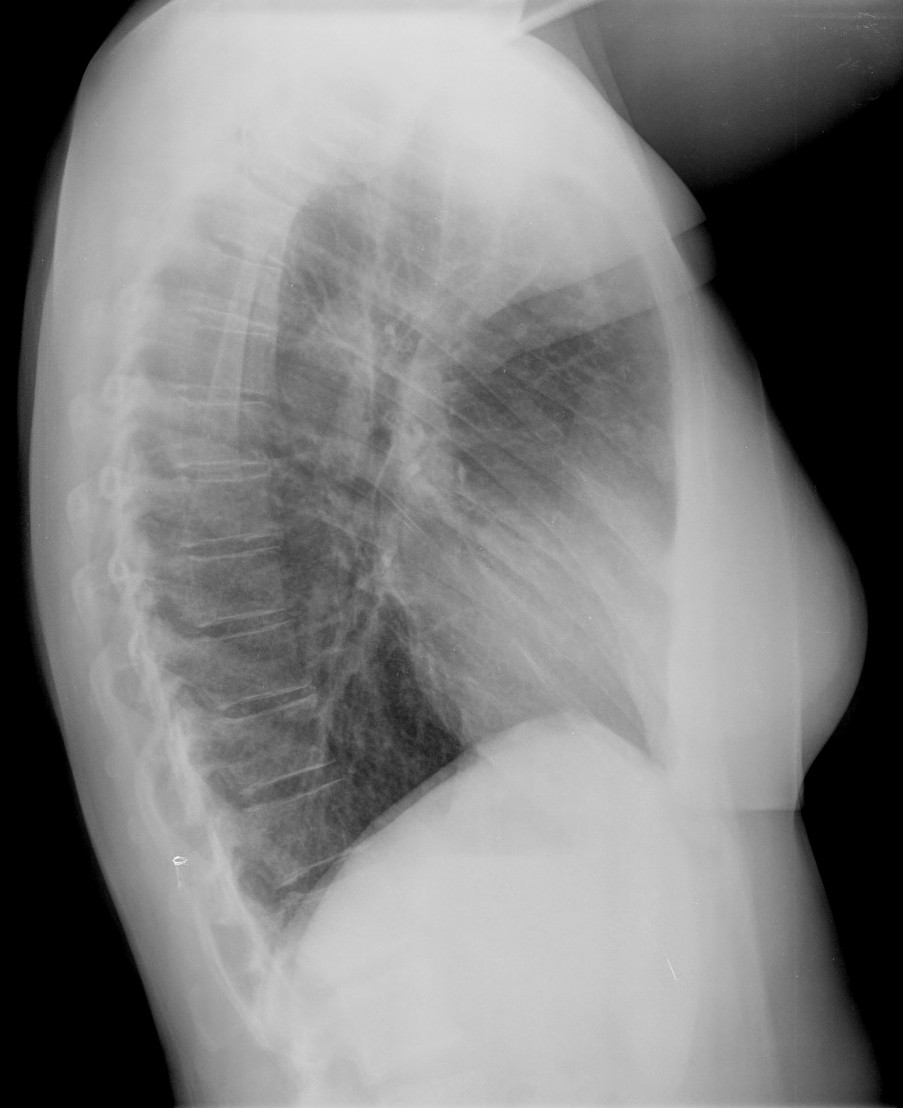

CASO: Febrícula y tos de 4 días de evolución.

Hallazgos:

- En la placa PA se observa una asimetría en los hilios pulmonares, el hilio izquierdo tiene una densidad aumentada.

- Tras examinar la placa lateral se observa un aumento de densidad en la columna que puede ser compatible con una condensación, es el signo de la desnificación vertebral.

SIGNO DE LA DENSIFICACIÓN VERTEBRAL: En la radiografía lateral normal, la densidad de la columna torácica tiende a disminuir desde la parte superior hasta el diafragma; la alteración de ese patrón por la presencia de una densidad superpuesta a la columna, indica la existencia de una consolidación pulmonar. Este signo adquiere especial valor cuando en la proyección posteroanterior la consolidación está oculta en el espacio retrocardíaco o en la base pulmonar.